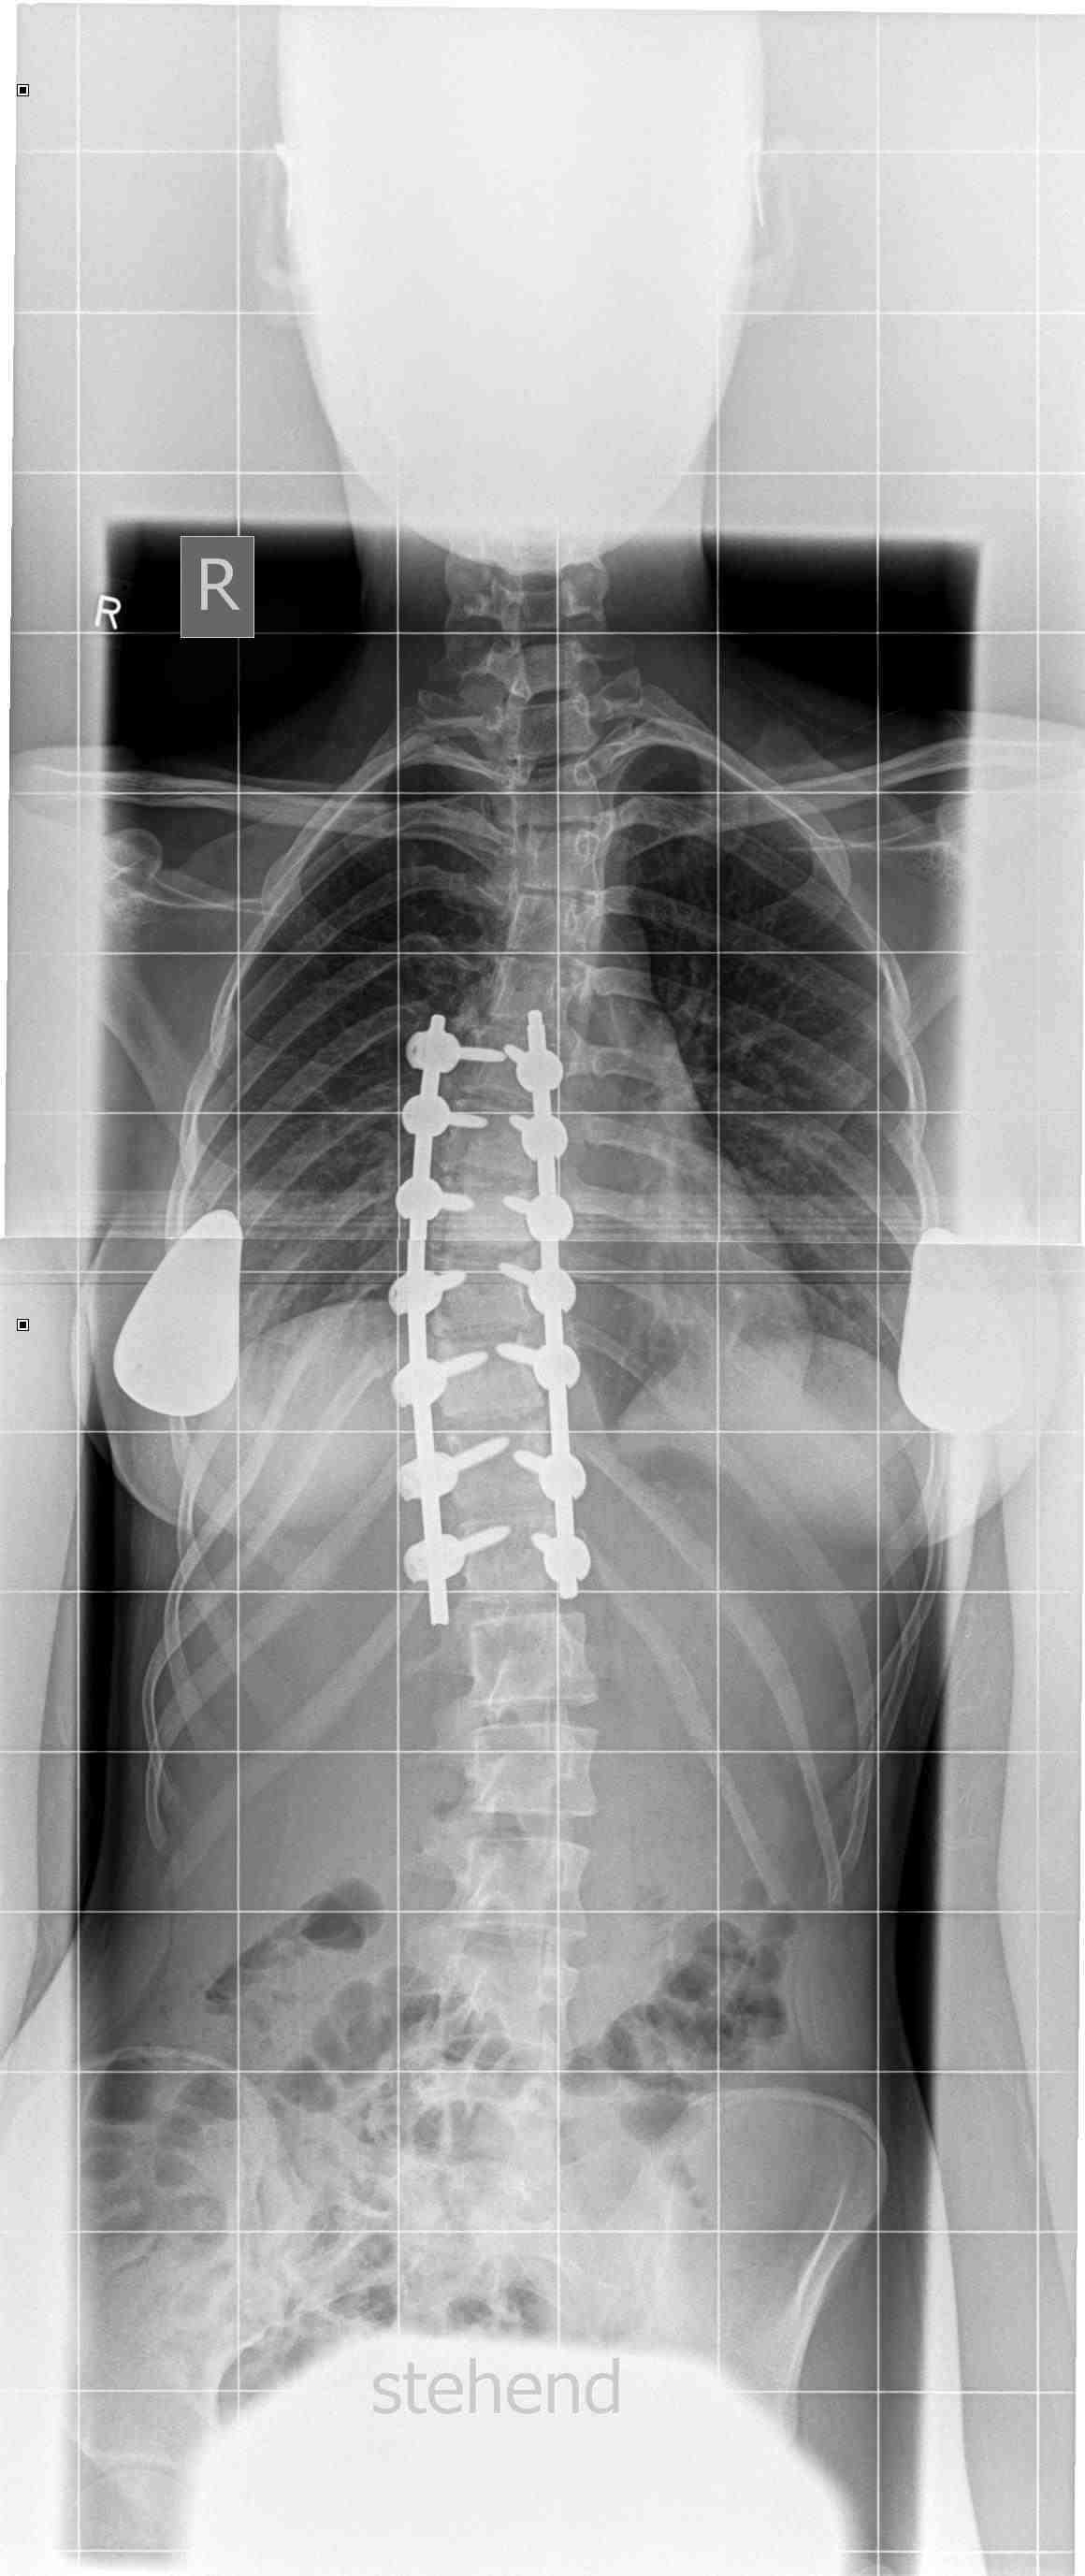

Die klassische Operationsmethode erfolgt von hinten mit sogenannten Schrauben- Doppelstabsystemen aus einer Titan- Legierung, ggf. in Kombination mit steiferen Chrom- Kobalt- Stäben, um bei schwergradigen, steifen Skoliosen eine bessere Korrektur zu erzielen. Diese Implantate sind CT- und vor allem MR- tauglich, d.h. eine diagnostische Schnittbildgebung des Körpers ist auch nach solchen Operationen weiter möglich.

Prof. Halm: Die Operationsergebnisse sind mit den verfügbaren, ausgereiften Korrektursystemen bei idiopathischen Skoliosen, aber auch anderen Skoliosetypen sehr gut geworden. Anhand von Messinstrumenten konnten wir u.a. in einer Registerstudie der Deutschen Wirbelsäulengesellschaft bei unseren Patienten gute bis sehr gute Verbesserungen der Lebensqualität feststellen. Ein Jahr nach der Operation erlaube ich allen Patienten wieder jeglichen Sport, den sie ausüben wollen. Die Komplikationsraten sind sehr gering geworden. Neurologische Störungen, insbesondere die gefürchtete Querschnittlähmung sind extrem selten, statistisch bei idiopathischen Skoliosen bei ca. 0,5%. Wundheilungsstörungen und Infektionsraten liegen bei etwa 2%. Auch Implantatbrüche und Korrekturverluste mit dem Risiko der Nachoperation sind bei diesen sehr häufigen idiopathischen Skoliosen des Jugendlichen selten geworden. Bei Grunderkrankungen bzw. bei Skoliosen des älteren Erwachsenen sind die Komplikationsraten höher und unbedingt vorab mit dem Operateur individuell zu erörtern, um eine Risikoabwägung durchführen zu können. Andere allgemeine Operationsrisiken sind wie bei jedem operativen Eingriff möglich, recht selten. Eine sorgfältige OP- Aufklärung ist essentiell und erfolgt bei uns meist mehrfach.